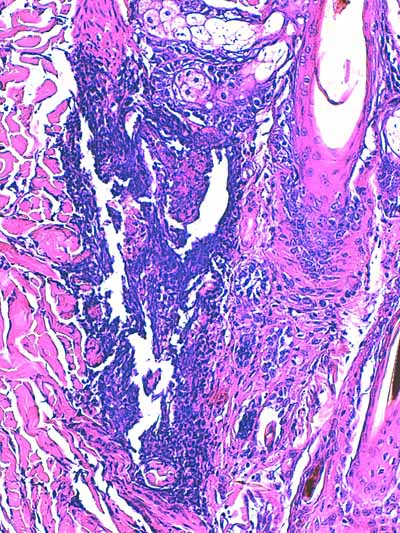

Photo 3 (Hémalun Eosine X 100) : l’épiderme se désengrène, une vésicule

sous-épidermique se forme. Le derme superficiel est œdémateux. Deux plages cellulaires dermiques

sont en étroit rapport avec des annexes folliculo-sébacées, dont une apparaît rompue.

Légendes de la Photo 3 :

- Ovales jaunes : plages cellulaires inflammatoires dans le derme périannexiel

- Flèche turquoise : follicule pileux rompu en rapport avec une plage inflammatoire

- Flèches jaunes : épiderme fragilisé qui se désengrène du derme

- Double flèche orange : épaisseur épidermique

- Double flèche verte : épaisseur dermique

- Double flèche bleue : épaisseur hypodermique

- Flèche orange : une vésicule sous-épidermique se forme